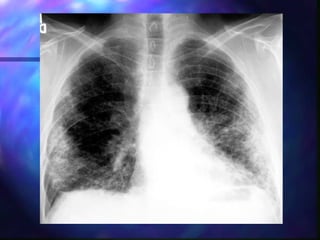

Diagnosis

s   Diagnosis is often suggested by history, chest

radiograph and high resolution CT scan of the

lungs.

Stage I

(bilateral hilar adenopathy)

Stage II

Reticular nodules and BHL